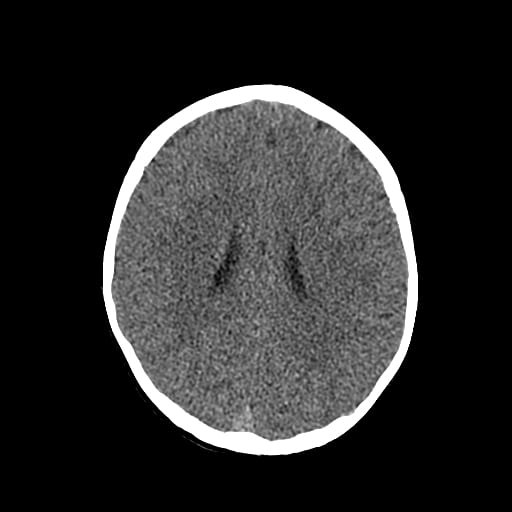

Age: 1

Sex: Male

Indication: Fall